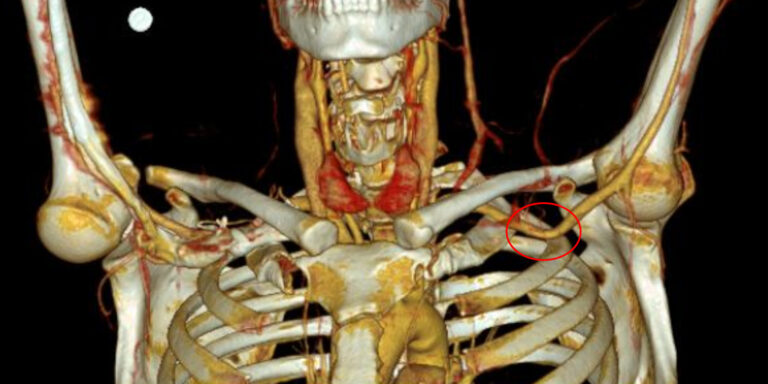

Im vorliegenden Fall des 39-jährigen Tennisspielers konnte ein neurogenes TOS ausgeschlossen werden. Eine CT-Angiographie unter Provokationsstellung konnte das duplexsonographisch vermutete arterielle TOS bestätigen. Das arterielle TOS repräsentiert mit 1 % die seltenste der drei TOS-Entitäten (neurogen, venös, arteriell). In den Händen von erfahrenen TOS-Chirurgen widerspiegelt die operative Dekompression mit einem transaxillären Zugang den therapeutischen Goldstandard, wobei mit einem medianen «Return-To-Sports» von 9 – 10 Monaten gerechnet werden muss. Gemäß amerikanischen Daten erreichen betroffene Baseball-Pitcher auch drei Jahre nach operativer Dekompression wieder präoperative maximale Wurfgeschwindigkeiten von rund 150 km/h [2].

M. pectoralis minor (M. pectoralis minor Syndrom).